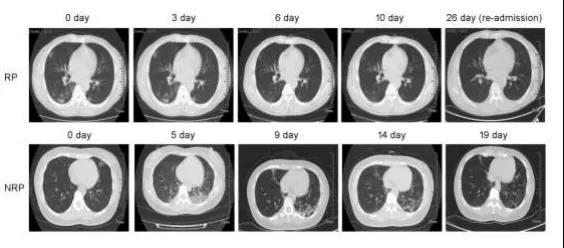

然而,与NRP患者相比,85.2%的RP患者胸部CT影像学持续缓解,其中36.2%在首次住院期间曾表现出短暂进展。

所有轻症患者均恢复,中症患者中37.0%的胸部CT成像正常,无炎症迹象,但63.0%具有稳定或减少的炎症迹象。